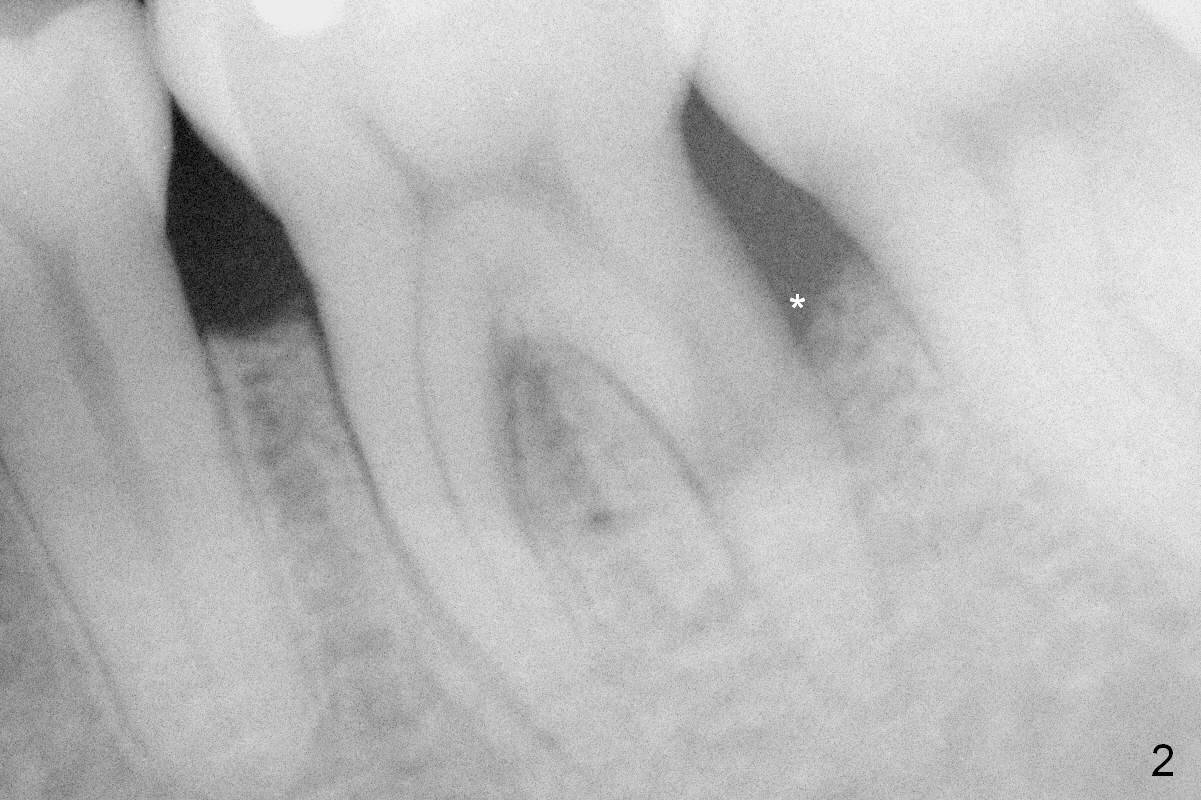

The mesial and distal crests of the tooth #19 were even for a 50-year-old man 7 years ago. Three years later, swelling developed around the distal root with bone loss (Fig.2 *). Three months later, localized swelling occurred (Fig.3 *) with oozing. The patient had thrombopenia (platelet 40 K). The tooth was extracted with suture. There is distolingual root tip resorption. Two months and a half later (Fig.4), a 6x17 mm implant was placed (Fig.5). The implant osteointegrated 5 months postop (Fig.6). The distal crest re-appears 5 months (Fig.7), 2 years (Fig.8) and 2 years 8 months (Fig.10) post cementation. At the last appointment, the patient complained of pain and swelling at #30 with mesial bone loss (Fig.10 *), as compared to Fig.9 taken 9 years ago. The mesiolingual pocket is deep. After scaling and Chlorhexidine irrigation, Arestin is locally administered.